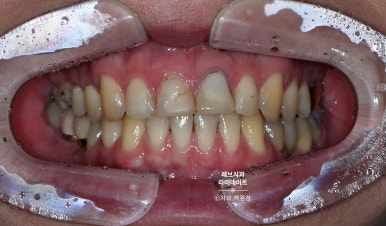

오늘 소개해드릴 환자분은 앞니의 충치 때문에 이미 여러번 레진치료를 받았던 환자분이었습니다.

아시다시피 레진이라는 재료는 '다공성'의 재료이기 때문에 매끈해보여도 현미경으로 보면 표면에 미세한 구멍이 많은데요, 그 때문에 변색에 취약한 재료입니다.

저희 병원에 내원한 유튜버셨는데요, 앞니가 특히 레진으로 덕지덕지 치료되어 있는 것을 보실 수 있습니다.

치아를 보존하는 것. 물론 중요합니다만... 레진 치료 위에 또 레진을 붙이고 붙이고... 이제는 치아의 절반은 레진이었고 변색되는 치아에 지쳐있는 분이셨어요.

깔끔한 남자분의 외모와는 달리 깔끔해보이지 않는 치아였습니다.

그래서 웃음도 마음대로 못짓는 안타까운 상황...